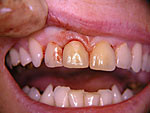

Die folgenden Patientenfälle sollen Ihnen einen Einblick in die Möglichkeiten der modernen Implantation geben.

Frontzahn-Implantation: